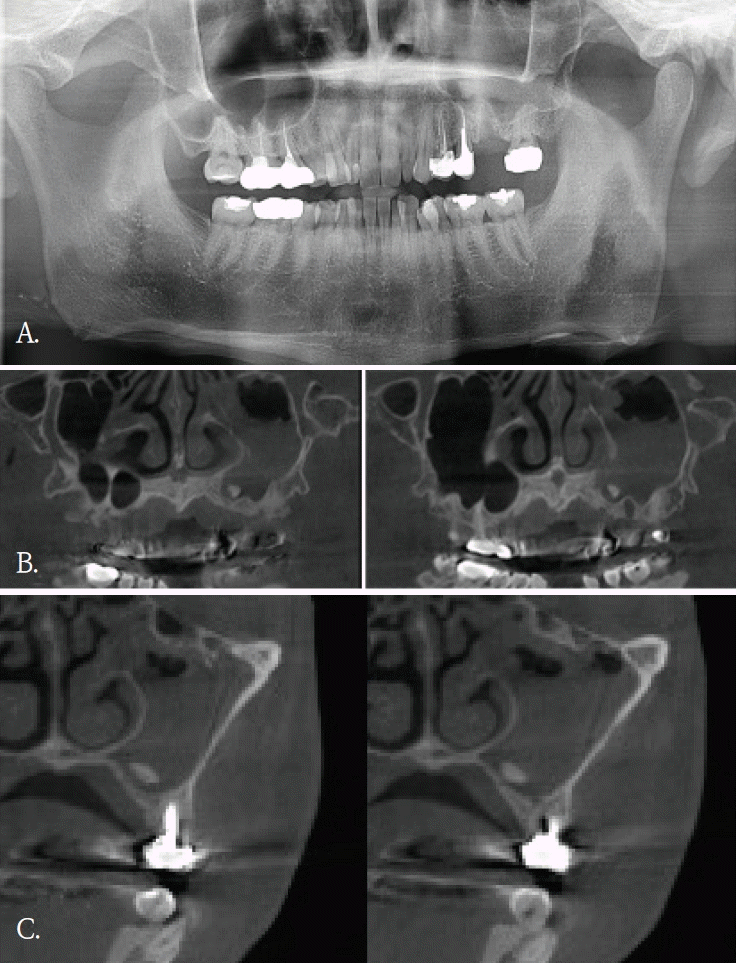

임플란트 식립 중 식립체가 시야에서 소실되어 위치 확인을 위해 60대 여자환자에서 파노라마방사선검사를 시행하였다. 파노라마방사선영상에서 임플란트 식립체로 추정되는 금속성 방사선불투과성 구조물이 우측 비강 부위에 중첩되어 관찰되었고 영상에서 비강 하연 부근에 위치한 것처럼 보였다(Fig. 4A). 이에 비강 및 상악 치조골과의 정확한 위치 관계를 평가하기 위해 콘빔CT 검사를 시행하였다. 콘빔CT에서 해당 구조물은 고음영 금속성 구조물로 확인되었으며, 상악 우측 전치부 측와 부위의 순측 연조직에서 관찰되었다(Figs. 4B and C). 또한 비강저 및 상악 치조골 피질골의 연속성이 보존되어 구조 발치와가 관찰되었다(Fig. 5A). 이러한 소견은 좌측 상악동 점막의 염증성 변화 가능성을 시사하였다. 상악동 병변의 범위 및 발치와와 상악동하연의 관계를 평가하기 위해 콘빔CT검사를 시행하였다. 콘빔CT에서 좌측 상악동 내에 연조직음영에 의한 혼탁이 관찰되었으며, 이는 상악동의 약2/3이상을 채우는 양상이었고 상악동 소공주변까지 연장되어 보였다. 또한, 상악동 전하방에서 경계가 명확한 작은 타원형의 균질한 고음영 구조물이 관찰되었으며, 골밀도에 해당하는 방사선불투과성 이물질로 판단되었다(Figs. 5B and C). 해당 고음영 소견은 파노라마방사선영상에서는 명확히 구분되지 않았다. 환자의 발치 병력을 고려할 때 해당 구조물은 상악동 내로 이동한 잔존치근이 의심되었으며, 외과적 제거를 시행하였다. 제거된 이물질은 상악동 내 잔존 치근으로 확인되었다.

Fig. 5.

A. Panoramic radiograph. An extraction socket of the left maxillary first molar is noted. Diffuse haziness of the left maxillary sinus is observed; no other definite abnormality is identified. B. Panoramic reconstruction, C. cross-sectional cone-beam computed tomographic images. Soft-tissue density nearly fills the left maxillary sinus. A small radiopaque foreign body is identified at the floor of the sinus.